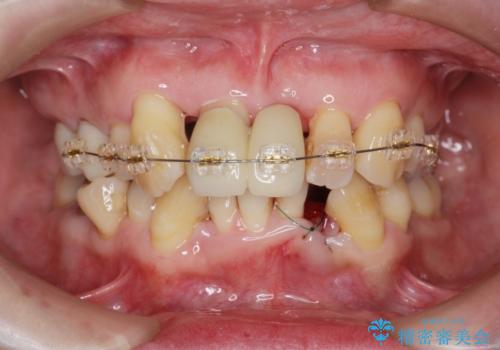

- 重度の歯周病に罹患しており、他院で「多数の歯を抜歯したのち、入れ歯を入れるしかない。」と言われ、入れ歯以外の方法がないか相談のため来院されました。

重度の歯周病で多数の歯を残せない問題、歯並び・噛み合わせの問題、欠損の問題、と多数の大きな問題が認められました。

このままの歯並びでは仮にインプラントを埋入したとしても歯ブラシがしづらく、また歯周病の問題が再発しやすい、と判断し矯正治療を行ったのちに歯周病治療、インプラント治療を行っていく治療計画としました。